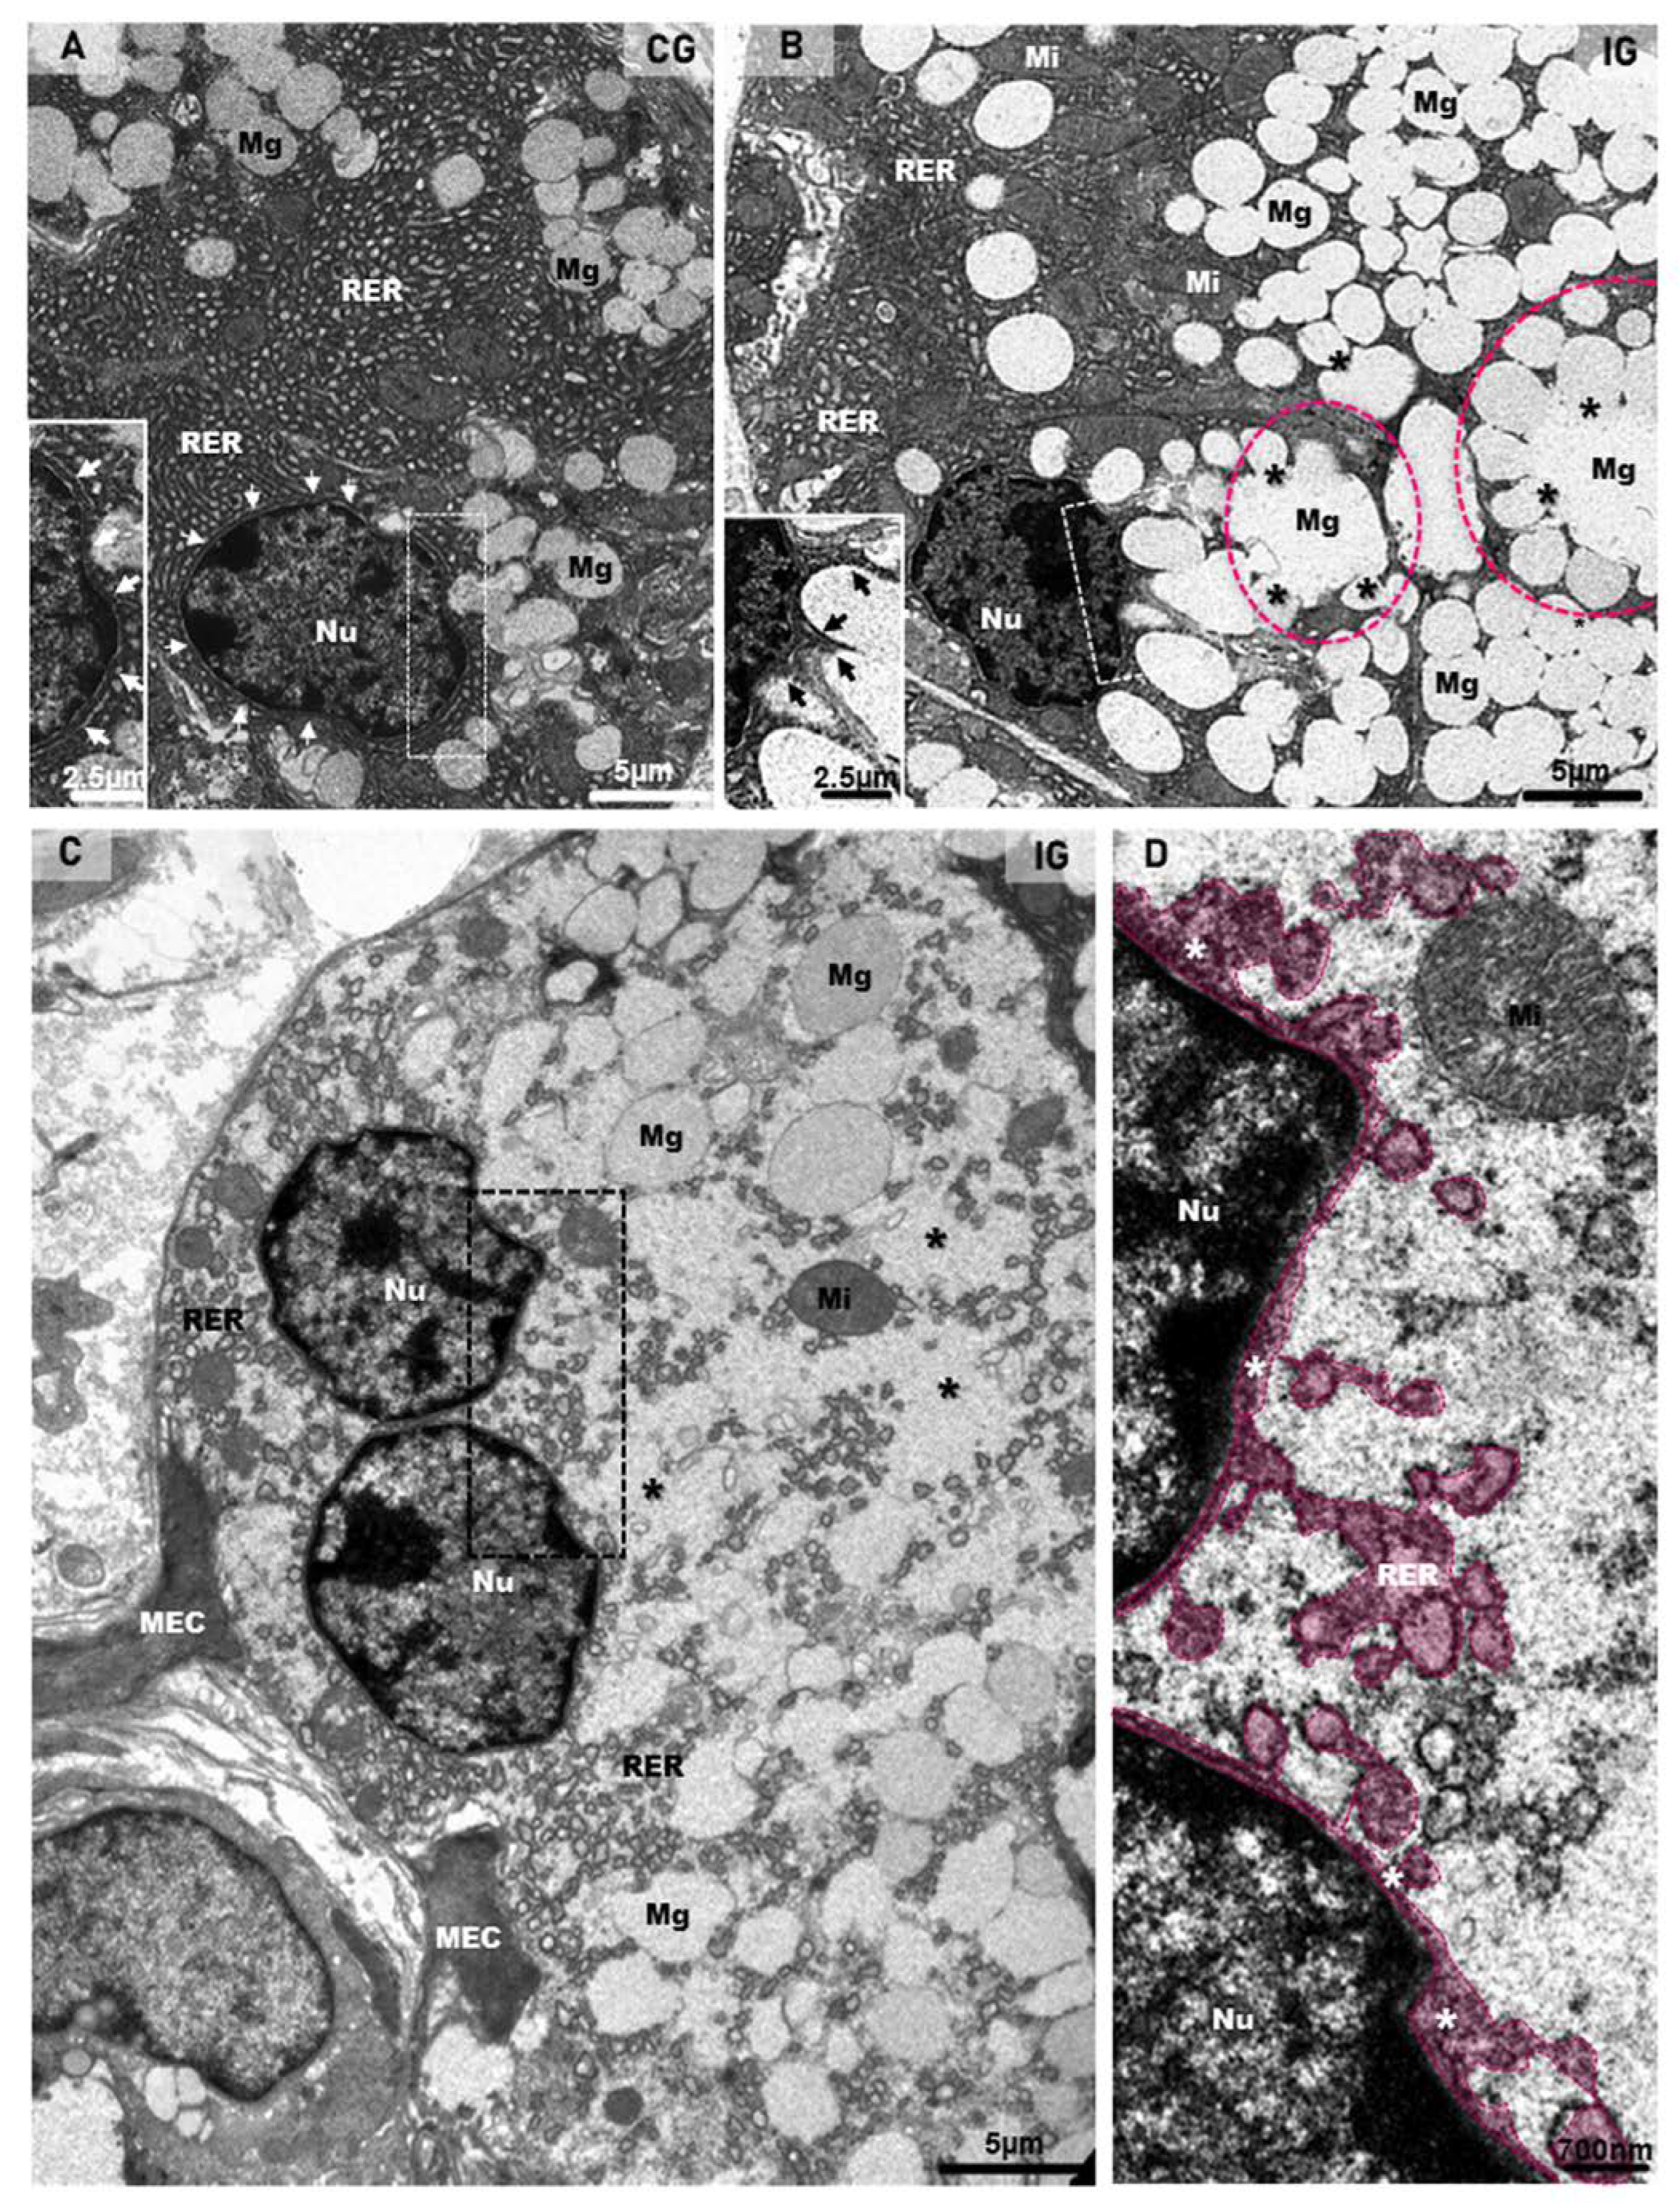

2.3. Ultrastructural Features Confirm Infection, Acinar Hypertrophy and GCT Compression

2.4. Viral Particles in Telocytes, MECs and Endotheliocytes